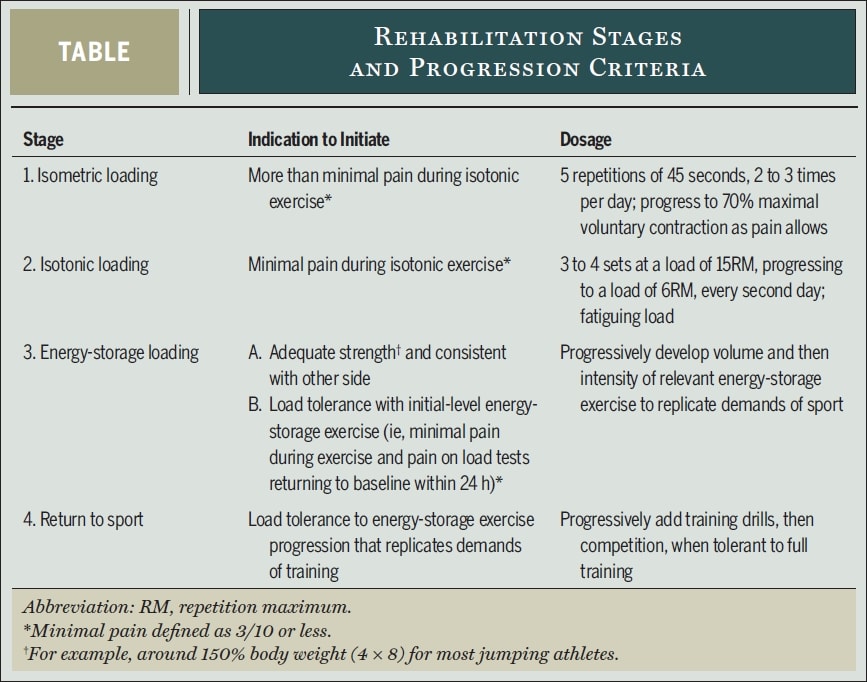

Так как же может выглядеть такая программа сопротивления с тяжелой медленной нагрузкой? Лучшие исследователи тендинопатии Питер Маллиарас, Джилл Кук, Крейг Пурдам и Эбони Рио предлагают следующий научно обоснованный 4-этапный протокол реабилитации в своей статье с сайта 2015:

В первую очередь следует модифицировать нагрузку, отменив высоконагрузочные действия по накоплению энергии, которые усугубляют боль. В случае с атлетами, которые находятся в середине сезона, объем и частота этих занятий должны быть снижены по согласованию с атлетом и тренером. Некоторая боль считалась допустимой во время и после упражнений, но симптомы должны были утихнуть в течение 24 часов после них. В своей работе Маллиарас использовал одно повторение одноногого падающего приседания до 90 градусов сгибания колена или максимального угла, допустимого по болевым ощущениям, в качестве болевого провокационного теста для определения переносимости нагрузки на ежедневной основе. Если оценка боли при нагрузочном тесте вернулась к исходному уровню в течение 24 часов после активности или реабилитационного сеанса, значит, нагрузка была переносимой. Если боль усилилась, значит, допустимость нагрузки превышена.

Давай подробнее рассмотрим каждый этап реабилитации:

Первая стадия - уменьшение боли: Изометрическая нагрузка

- 5 повторений в течение 45 секунд изометрического упражнения на квадрицепс одной ноги в среднем диапазоне (30-60° сгибания колена) при 70% МВПК 2-3 раза в день.

- Сопротивление следует увеличивать так быстро, как это терпимо.

- Испанское приседание

- Устрани другие недостатки силы по всей кинетической цепи

Стадия 2 - восстановление мышечной массы и силы, а также вызывание адаптации сухожилий: Изотоническая нагрузка

- Когда квадрицепсы можно будет нагружать изотонически без боли, превышающей NRS 3/10, можно приступать к этому этапу.

- Тяжелые медленные упражнения с сопротивлением в диапазоне от 10° до 60° сгибания колена вначале и прогрессируют до и более 90° сгибания, если позволяет боль. К ним относятся жимы ногами, приседания, хакк-приседания, сплит-седания и разгибания коленей в приседе. Изначально делай выпады на две ноги и переходи на выпады на одну ногу, как только позволит боль. Конгсгаард и др. использовали от 3 до 4 сетов каждый второй день при сопротивлении, соответствующем 15ПМ, и прогрессировали до 6ПМ. Продолжай упражнения первого этапа в дни между выполнением тяжелых упражнений с медленным сопротивлением.

Этап 3. Нагрузка на накопитель энергии: Повышай устойчивость к нагрузкам и улучшай мощность

- Когда достигнута хорошая сила и атлет переносит нагрузки на одну ногу с весом около 150% от веса тела (например, 4 сета по 8 повторений жима одной ногой), можно приступать к этой фазе, если в течение 24 часов после тренировки не наблюдается боли, превышающей NRS 3/10.

- Инициативой может стать двусторонний жим ногами с нагрузкой в 3 раза больше веса тела (или в 1,5 раза в случае с одной ногой), так как это оказывает на надколенник силу, соответствующую силе, возникающей при приземлении с вертикального прыжка.

- Прыжковые последовательности с остановками, прыжками и приземлениями, ускорением и замедлением, разрезанием и изменением направления движения

- Объем (количество прыжков, контактов) прогрессирует раньше, чем интенсивность (высота, скорость).

- Выполняй каждый третий день и продолжай изометрическую нагрузку и изотоническую нагрузку каждый второй и третий день.

Стадия 4 - возвращение в спорт

- Постепенное возвращение к тренировкам и соревнованиям, когда первоначально тренировки соответствуют объему и интенсивности упражнений третьего этапа, а затем переходят к объему и интенсивности, которые требуются в конкретной спортивной ситуации.

- Поддерживай упражнения 2-й ступени как минимум два раза в неделю и, в конце концов, упражнения 1-й ступени до или после тренировки.